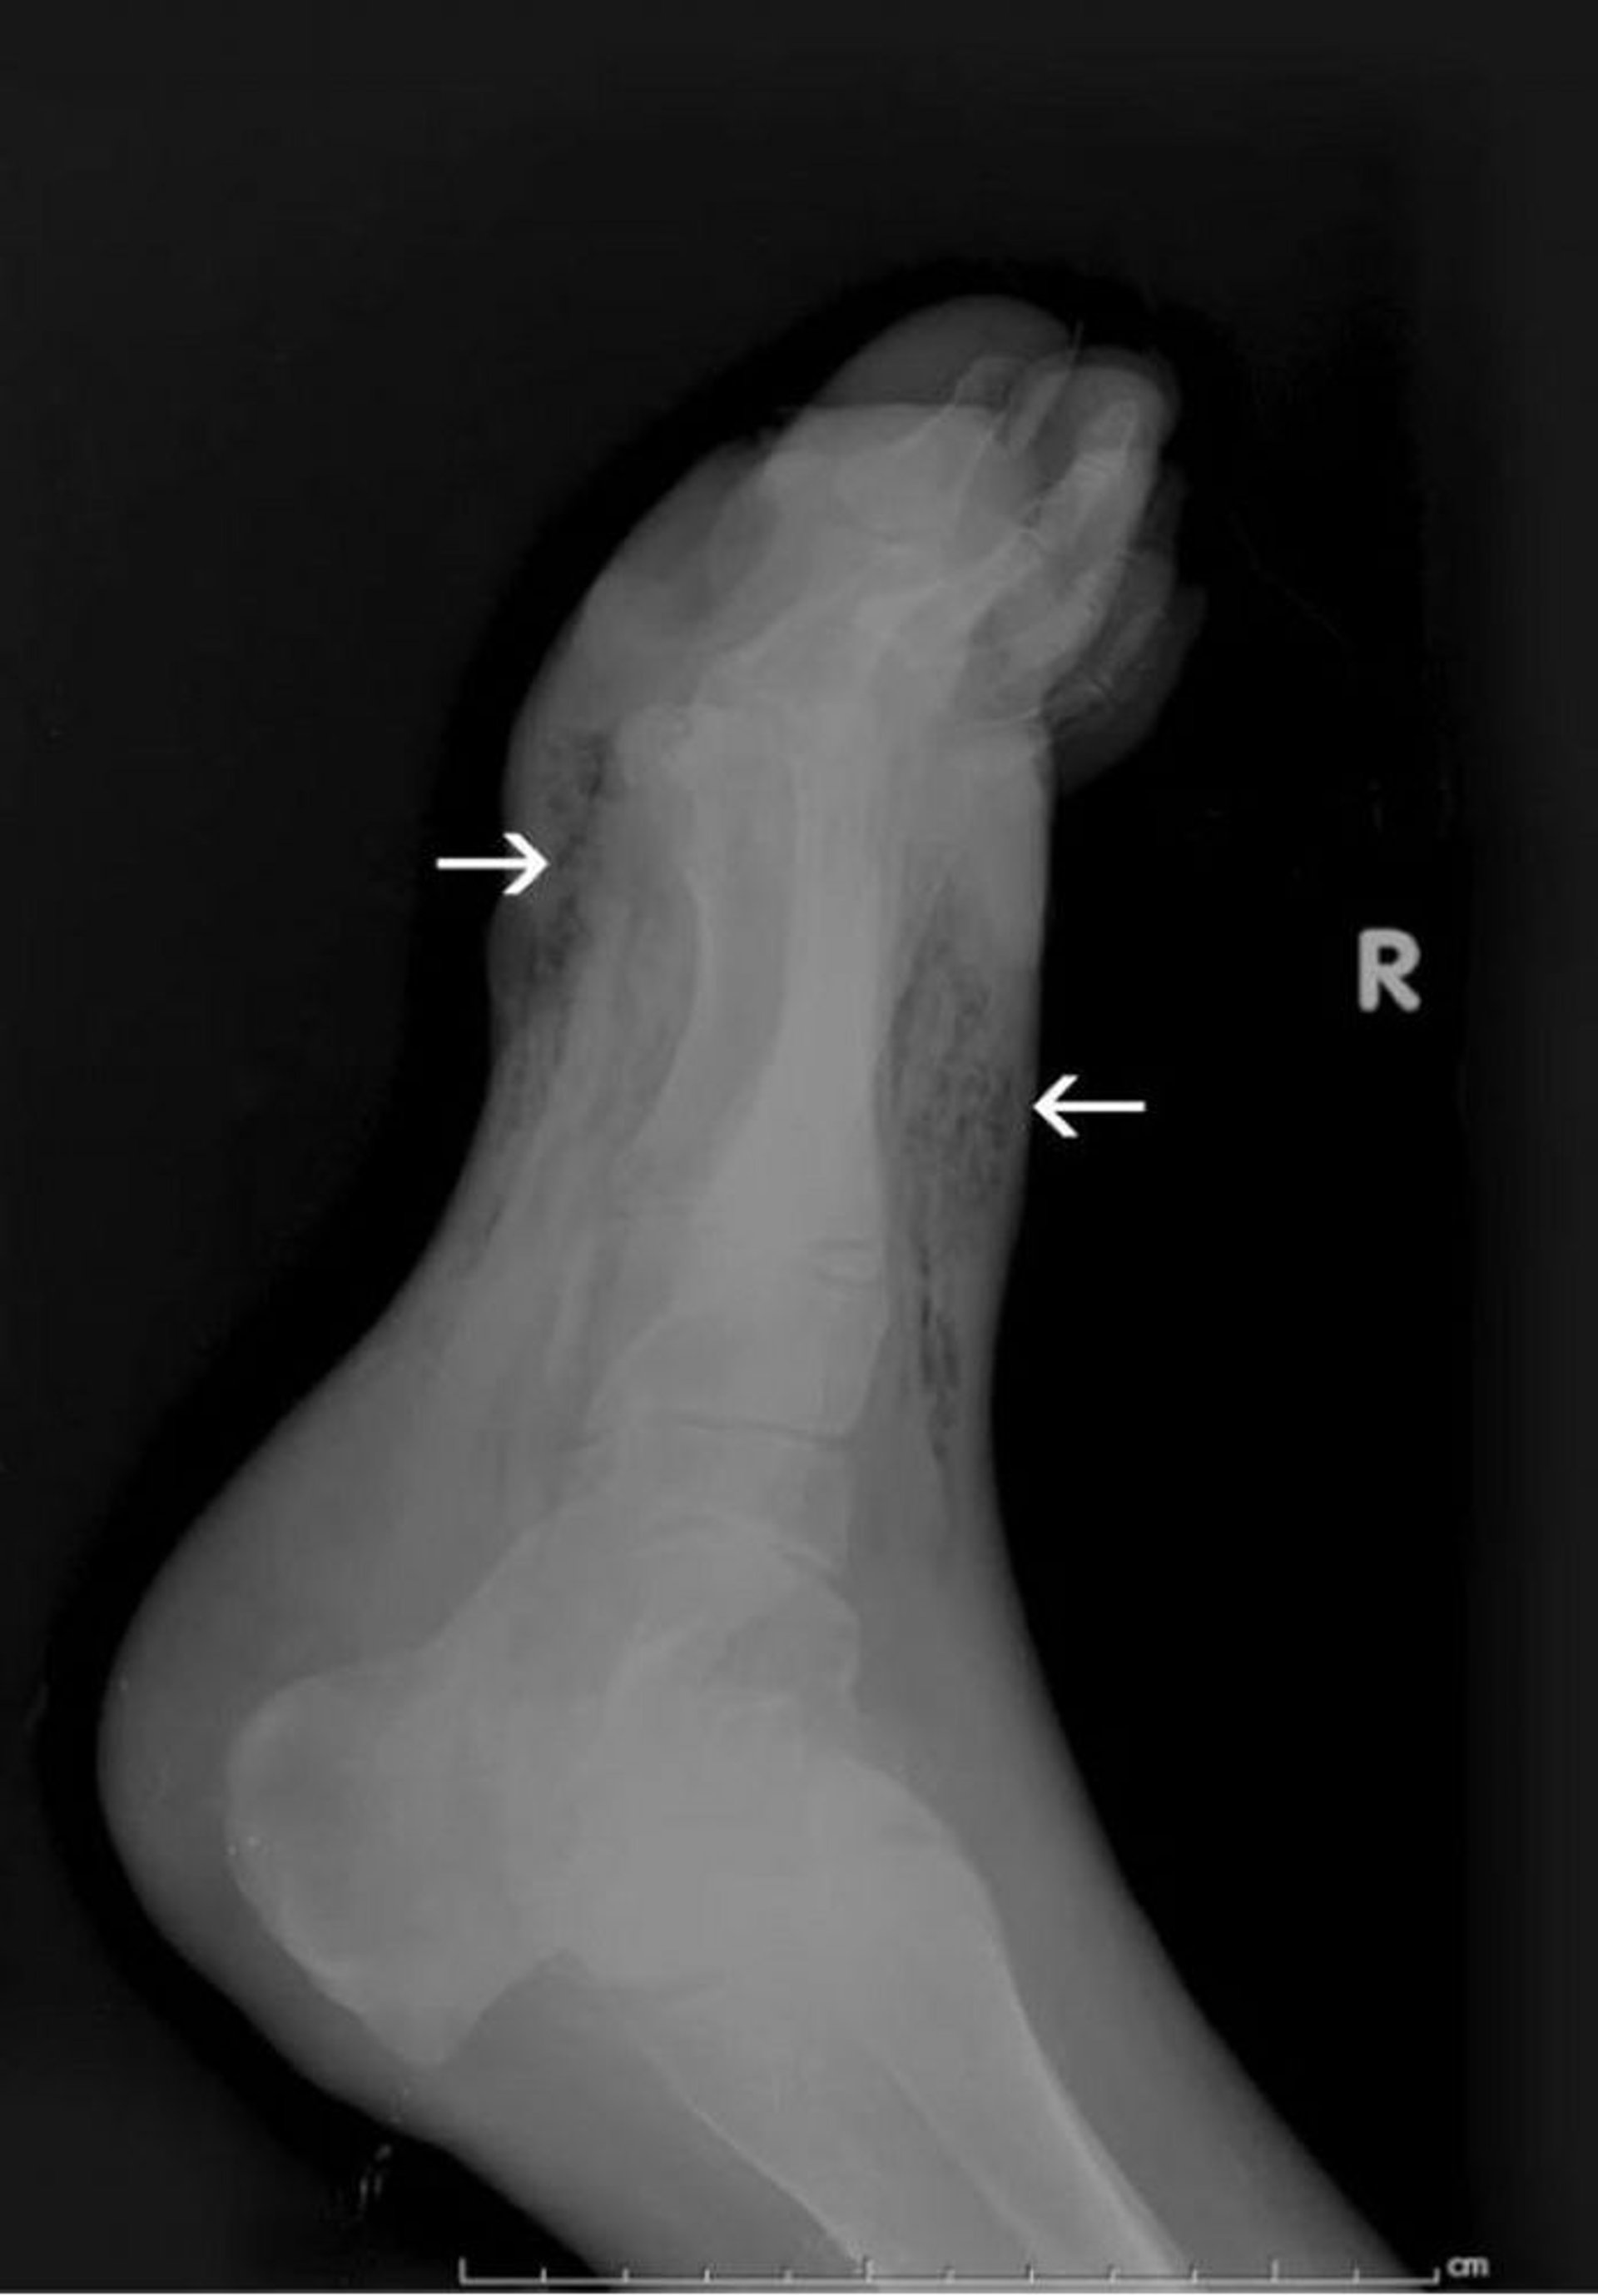

Gangrena del piede (RX)

Questa RX mostra gas nei tessuti molli del piede (frecce).